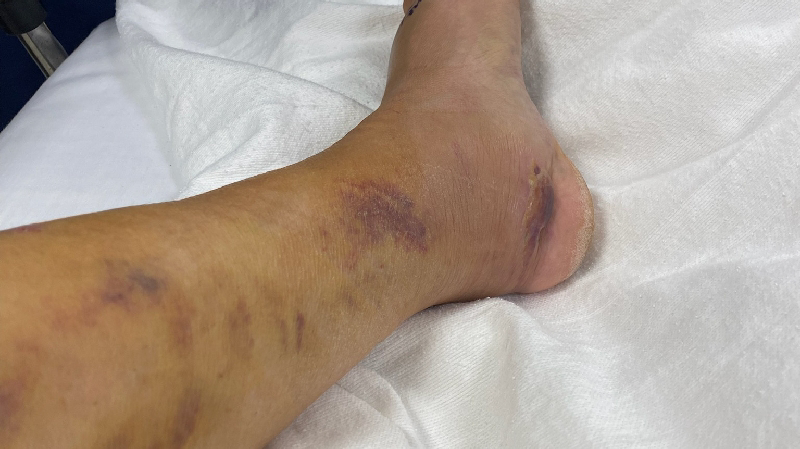

she's been working hard all her life but unfortunately a year and a half she had this unfortunately accident that she broke her heel bone in pieces she was ready to buy her dream house right before this accident happened now she spent all her savings in this situation and now she needs another surgery because the screws are coming out and she can potentially get the bone infected and high risk to get her foot amputate . . she cannot get social security and not disability because she worked with 1099 .. she needs help to keep up with rent and bills and she's terrified to get evicted most because she have two puppies that she needs to protect , and Plus she's been dealing with depression , she's in a good attitude and hope , from my heart thank you. Alma